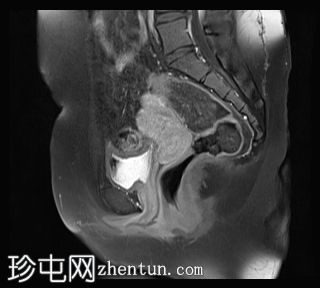

矢状位

T2加权像

双侧卵巢位置接近(卵巢相吻),左侧卵巢内可见一边界清晰的囊性病变,大小约3.1 × 2.7 × 2.9 cm,T1加权像呈高信号,T2加权像可见暗点征及内部暗点征。以上MRI特征符合卵巢子宫内膜异位囊肿的诊断。

右侧卵巢可见一囊肿,大小约为 2.8 × 2.0 × 2.2 cm,T1 加权像呈高信号,囊内可见液-液平面,提示囊内含有不同时期的出血性物质。由于对侧卵巢存在典型的子宫内膜异位囊肿,且该囊肿无强化,影像学表现强烈提示为另一子宫内膜异位囊肿。

子宫大小、轮廓及信号强度均正常,子宫内膜分区结构完整。未见局灶性肌层病变,子宫内膜厚度在正常范围内。

左侧盆腔可见少量游离液体。